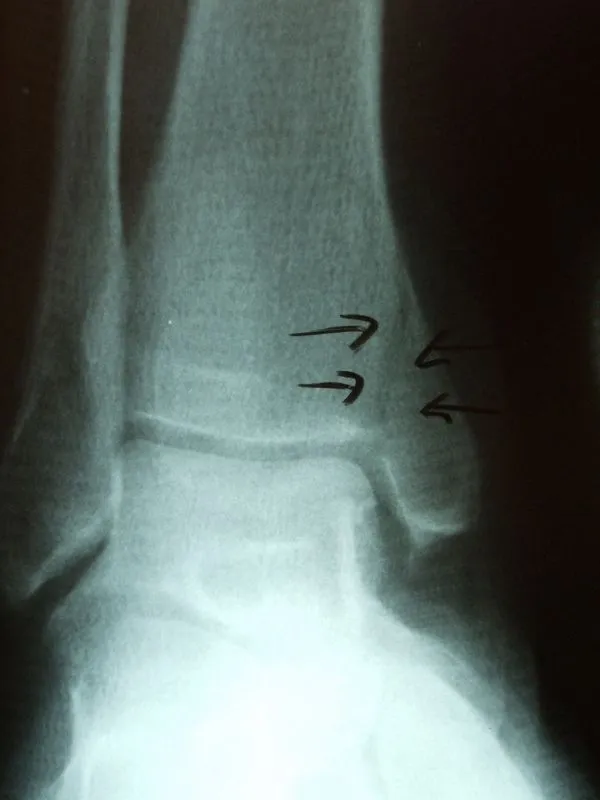

This is a picture of a medial malleolar stress fracture prior to percutaneous screw fixation

This is the same fracture seen on X-ray... the dreaded black line